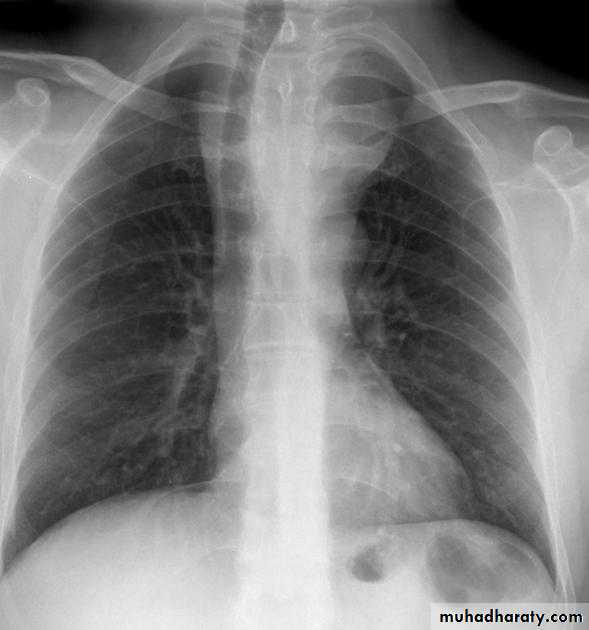

CXR of adult male PA and lateral views, it shows :Normal both lung fields ,Central cardiac shadow, Central trachea, central mediastinum, No boney lesions, no soft tissue abnormalitiesnormal radiologic anatomy of the chest Look carefully on both diaphragmatic cruse costo & cardio phrenic angles. Useful in detection of pleural effusion

10.normal chest anatomy